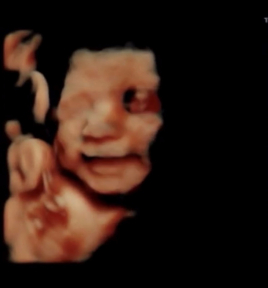

| 得意なお悩み | 冷え性・手足の冷え / 不妊・妊活 / 逆子 |